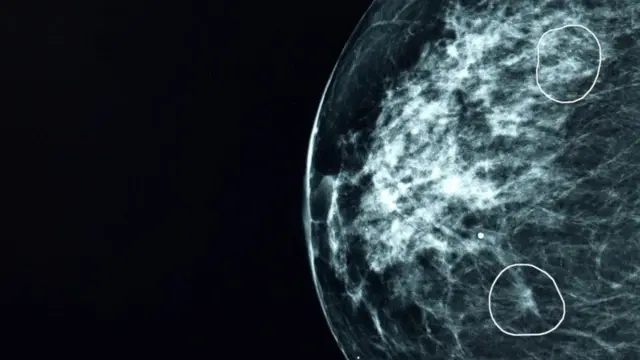

یک برنامه آزمایشی در بریتانیا نشان داد که فناوری هوش مصنوعی می‌تواند نشانه‌های اولیه سرطان پستان را حتی زمانی که از چشم پزشکان پنهان می‌ماند، شناسایی کند. این سیستم  میا (Mia) نام دارد. موفق شد در میان بیش از ۱۰ هزار ماموگرافی، سرطان ۱۱ زن را کشف کند که توسط رادیولوژیست‌ها نادیده گرفته شده بود.

سرطان پستان در مراحل اولیه معمولاً بدون علامت و بسیار ریز است. اگر تومورها در این مرحله شناسایی شوند، احتمال درمان موفقیت‌آمیز و بقای بیمار به بیش از ۹۰ درصد می‌رسد. نمونه‌ای بارز از این دست، زنی به نام باربارا بود که تومور شش میلی‌متری‌اش توسط میا شناسایی شد. او تنها با یک عمل جراحی و پنج روز پرتودرمانی درمان شد.